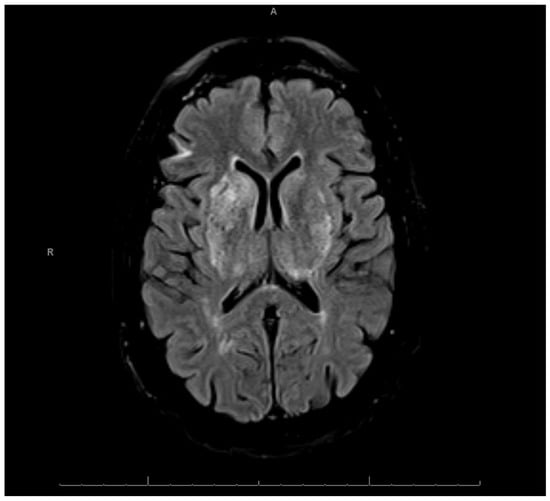

After managing the patient’s agitation, ceftriaxone and doxycycline were initiated to treat presumed community acquired pneumonia, antihypertensives were initiated to manage the patient’s marked hypertension, and intravenous thiamine was initiated prophylactically. Magnetic resonance imaging (MRI) of the brain was then completed, which demonstrated areas of restricted diffusion involving the bilateral hippocampi, thalami, putamen, and caudate nuclei (Figure 1, Figure 2, and Figure S1). This pattern was suspicious for cytotoxic edema resulting from hypoxic, ischemic, or toxic encephalopathy.

Figure 2. Lesions in Bilateral Thalami and Basal Ganglia. Diffusion-weighted brain MRI showing restricted diffusion in bilateral thalami, putamen, and caudate nuclei.